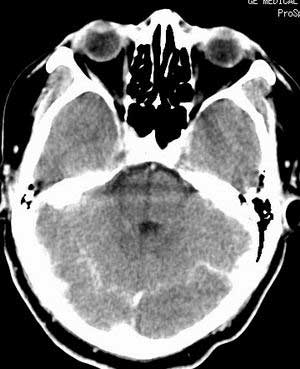

患者男,58岁。耳爆震伤后耳聋2年余,而后双耳道肿胀,间断性流脓。近一月来头痛、恶心、呕吐,右眼红痛,不能入眠。

在平扫时,见右侧枕骨下方小脑半球表面带状模糊稍高密度影,考虑为耳源性脑内感染。

双侧乳突蜂房密度呈气体样,慢性乳突炎可能性不大,

双侧颞叶脑实质密度均匀未见异常密度灶,

平扫右侧岩骨与枕骨交角内侧脑质内见淡片状密度增高影,内缘清晰。增强图象上未见明显显示。

考虑:1)伪影可能,建议复查头ct平扫。

2)加照头ct骨窗,以显示乳突气房内是否有病变。

最好能加照ct骨窗,观察右侧岩骨。

条状高密度为小脑幕吧

条状高密度为小脑幕

横窦乙状窦。